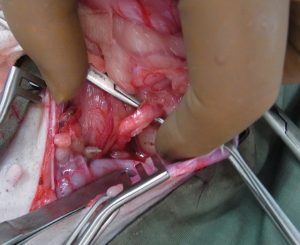

次に詰まっている尿管結石部位を探し出します。

切開を加えて、尿管結石を取り出しカテーテルにてフラッシュし膀胱までの通過に問題ないか確認しているところです。

狭窄しないように、縫合します。色々な縫合法がありますが、今回は切開線に沿って縫合しました。摘出した「尿管結石」です。